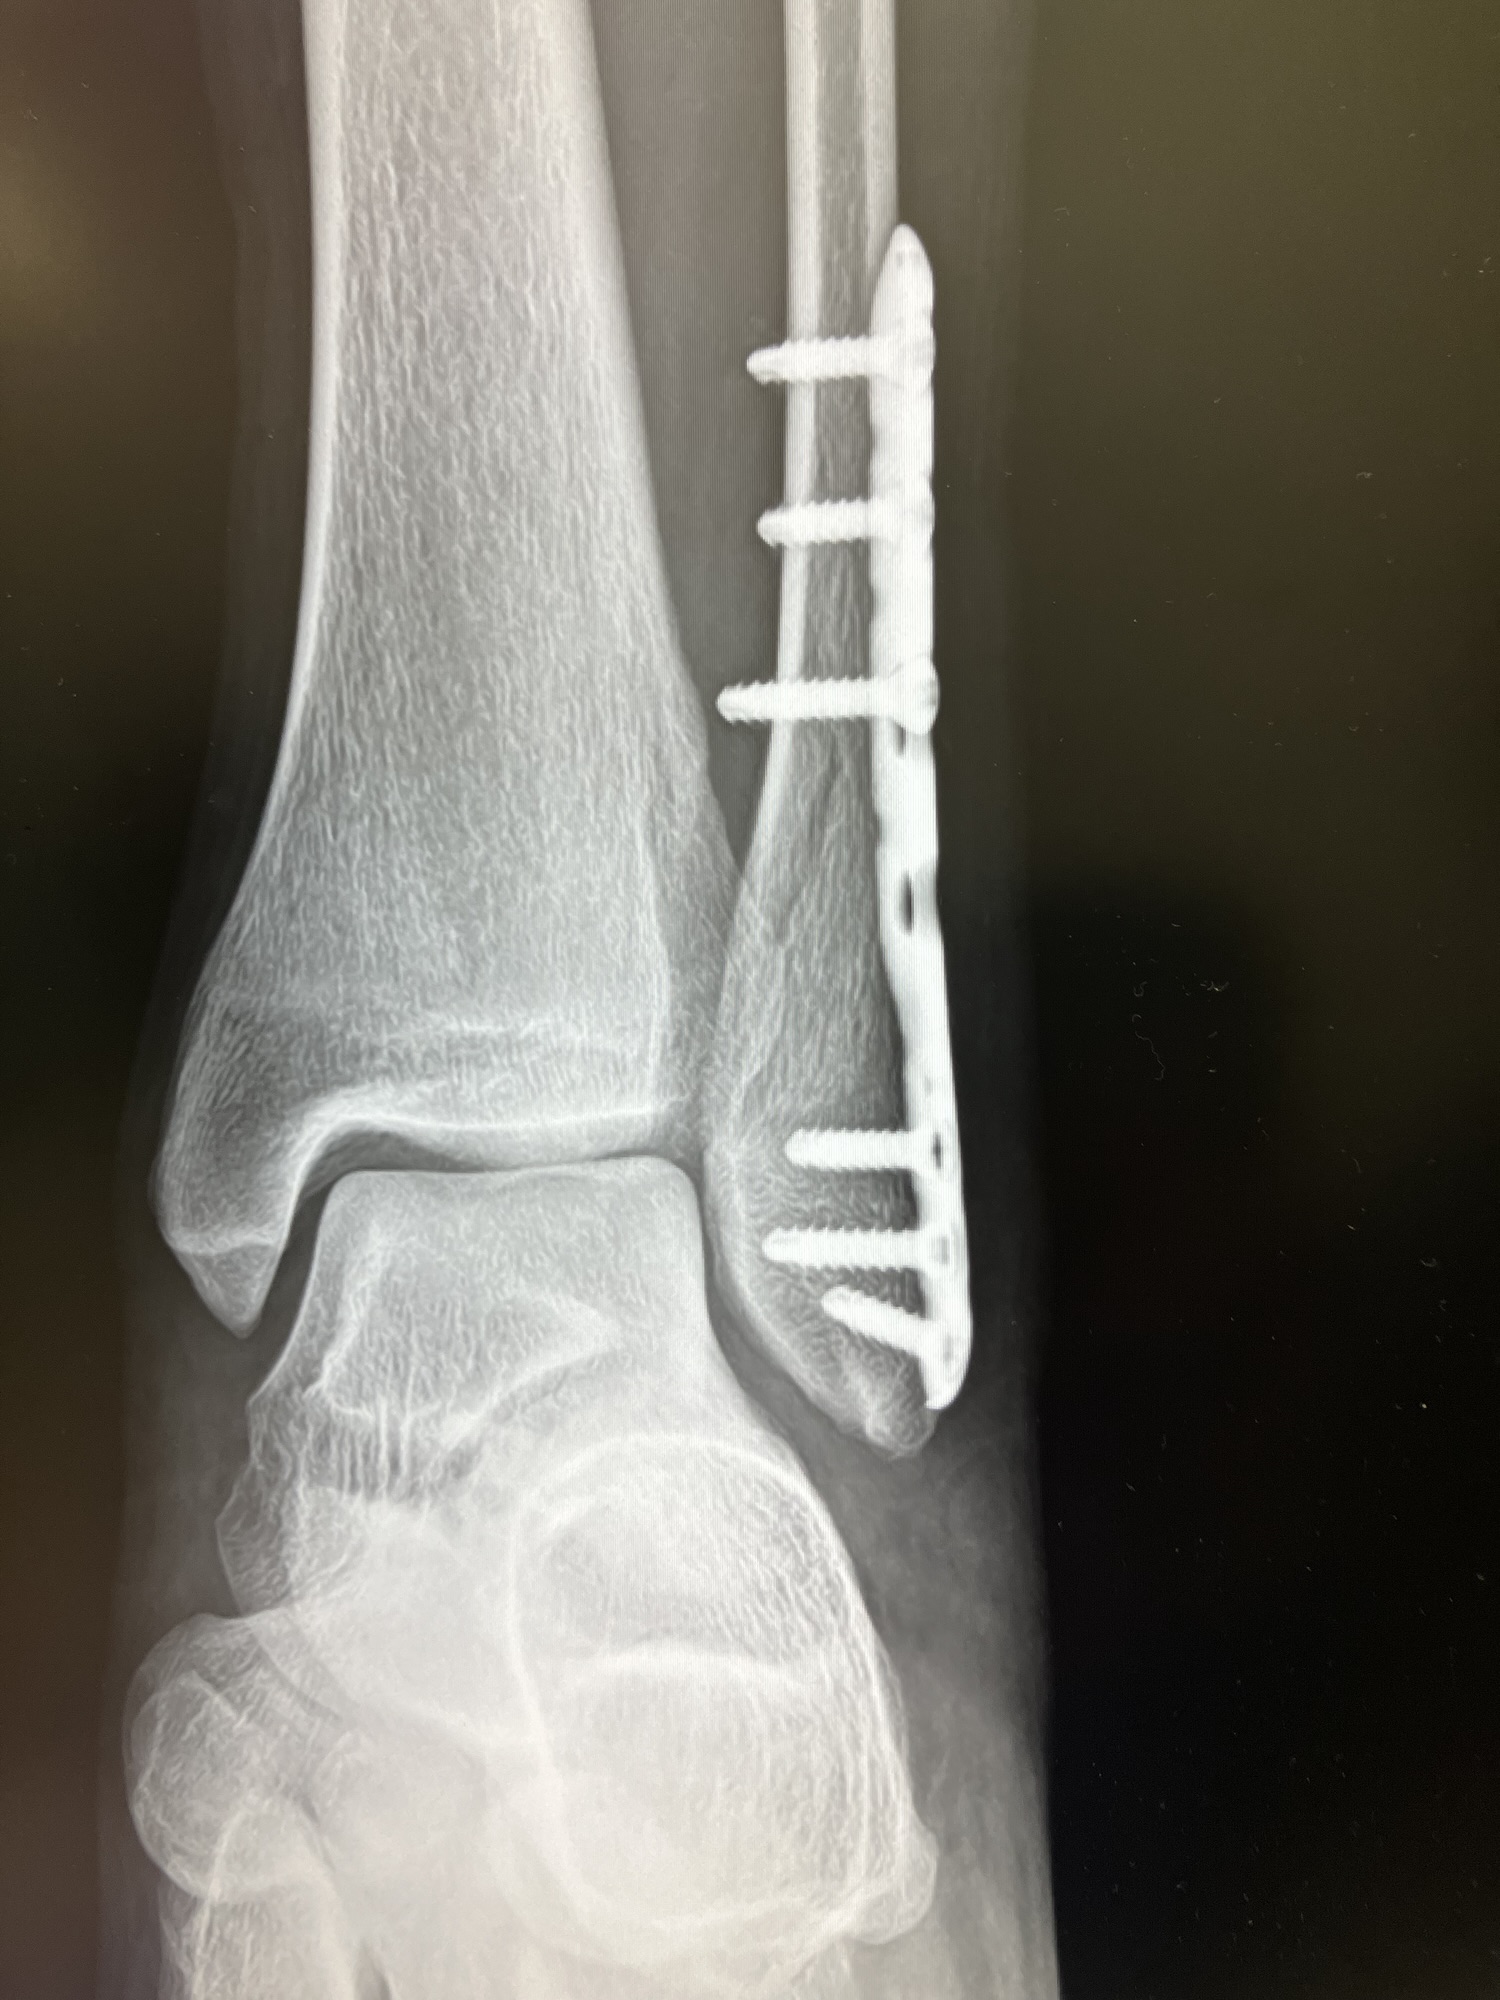

そのまま救急車で運ばれ、診断は「外果骨折」。

聞き慣れない名前ですが、足首らへんの骨折でした。

現在、足首には固定用の金属プレートが入っています。

将来これを抜くかどうか、なかなか悩ましいところです。悩んでます。